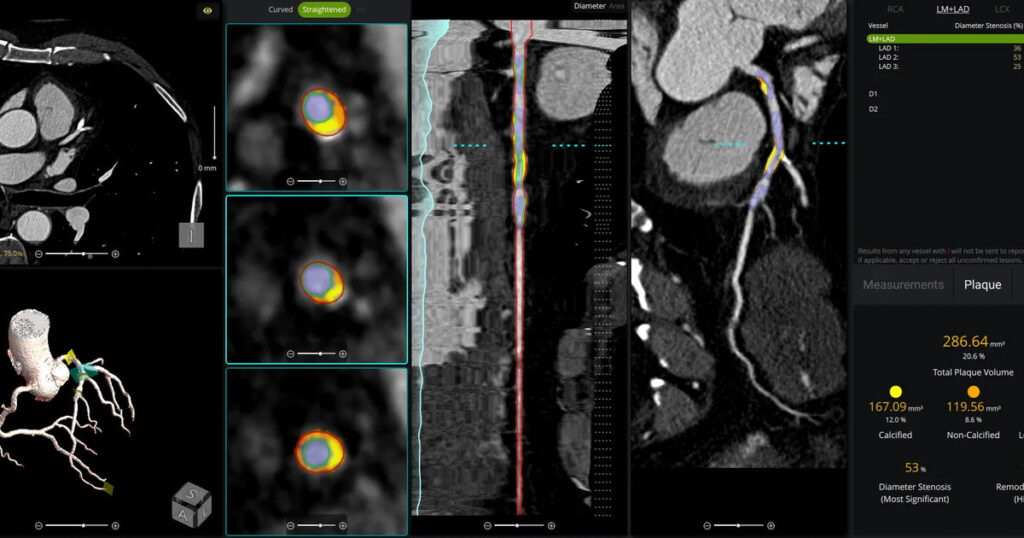

The use of AI to evaluate plaque buildup in CCTA images has been one of cardiology’s biggest ongoing trends. Implementing this software into existing workflows, however, can be a challenge. An upcoming webinar is focused on providing guidance to hospitals and cardiology practices hoping to learn more about this topic.Read More